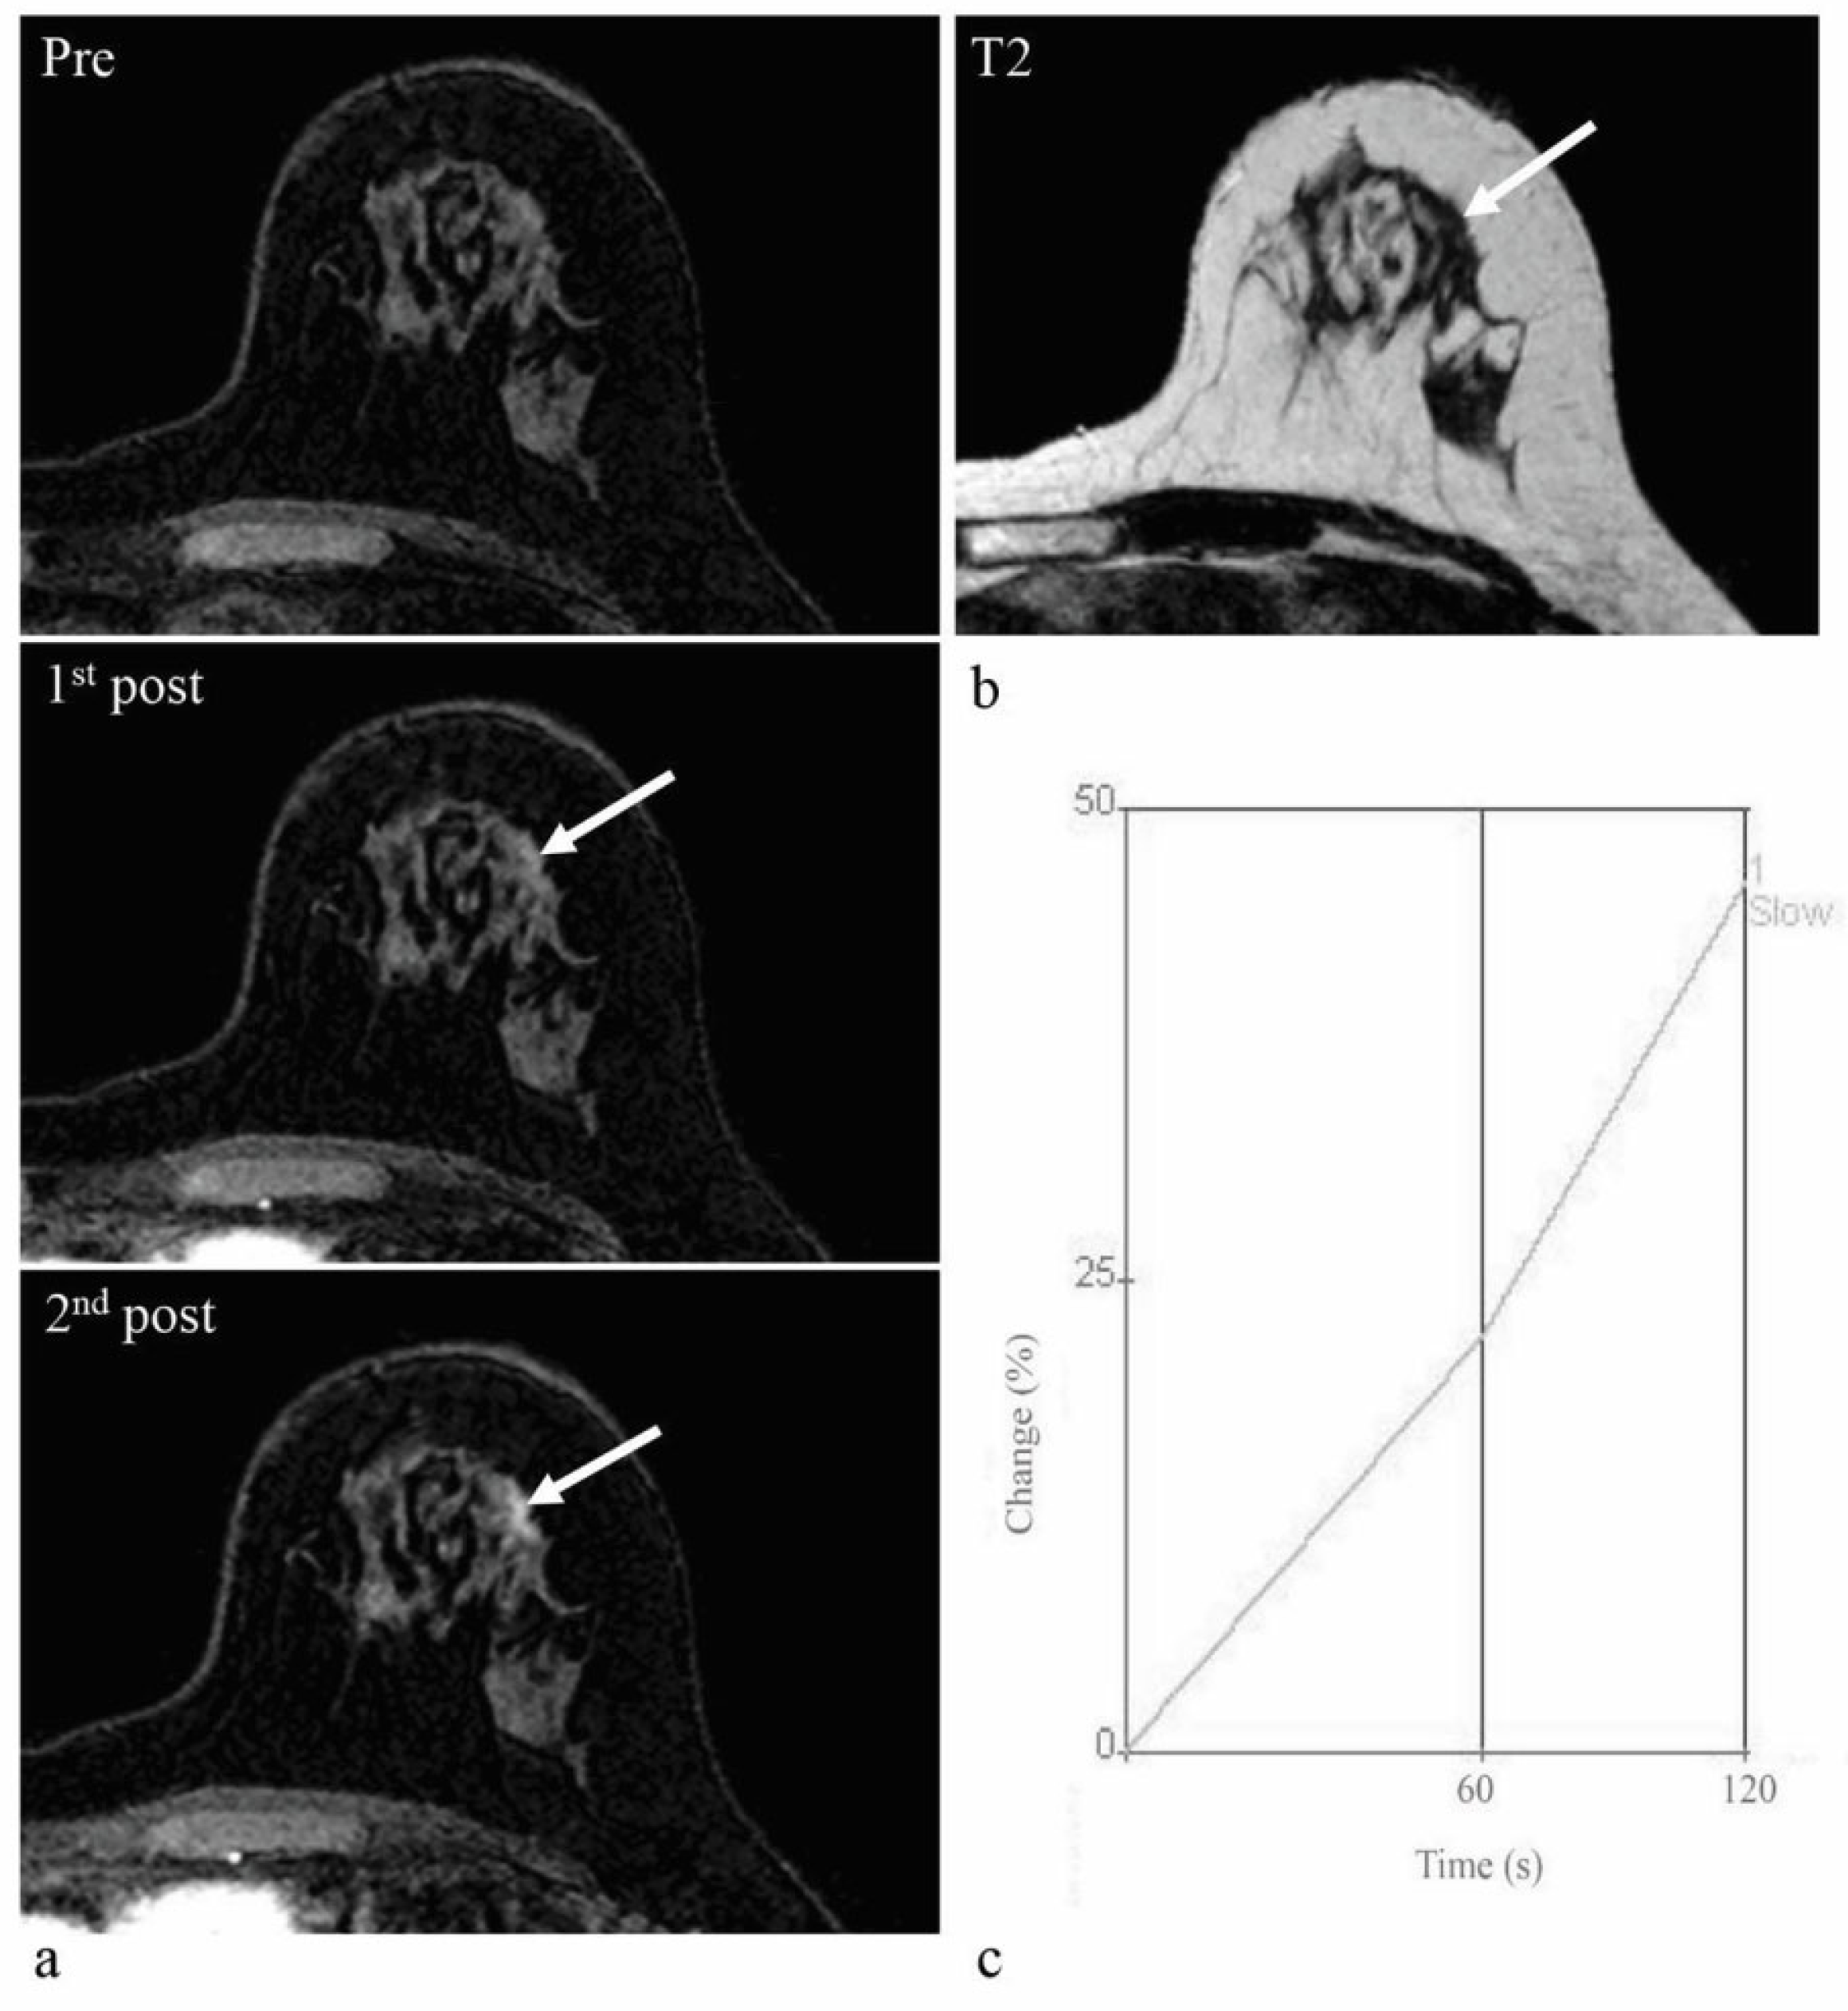

Figure 5.

Screening abbreviated breast MRI (AB-MRI) images of a 67-year-old woman with a history of right breast-conserving surgery due to breast cancer. Four years after surgery, pre-contrast and two post-contrast-enhanced axial images (a) show a 1.1 cm irregular enhancing mass (arrows) in the right breast at the operation site. The T2 signal intensity is not high (b). This lesion was assessed as BI-RADS 4C category in the original report. According to the interpretation guideline, it is classified as a suspicious lesion for which biopsy is recommended. However, kinetic analysis shows a low enhancement degree of 68% on the first post-contrast-enhanced image (c). This lesion was detected by second-look ultrasound (US) and confirmed as invasive ductal carcinoma by US-guided core biopsy and subsequent surgery. This is a false-negative case when the enhancement degree on the first post-contrast-enhanced image is combined with morphological analysis.